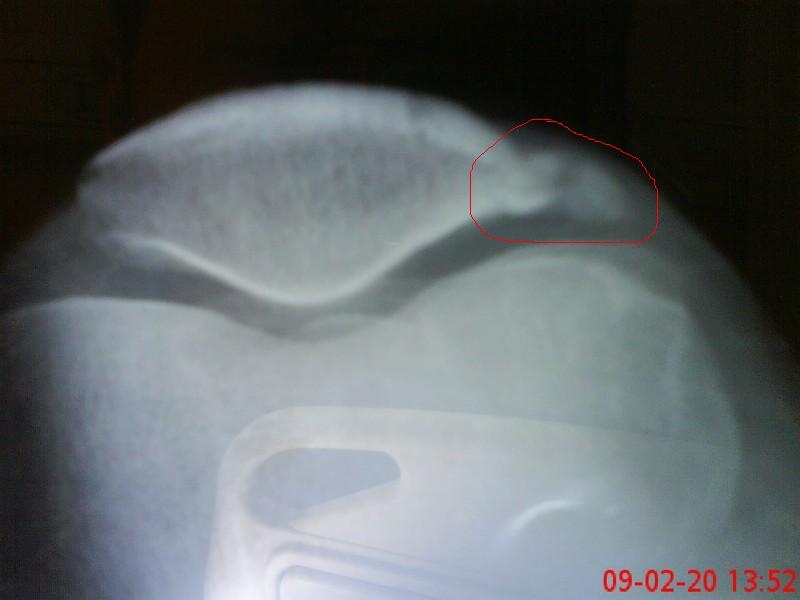

上三张片子,看看我的病根在那儿,圈起来那块是多出来的。。

做完手术的时候我问开刀的徐雁,他说是膑骨先骨折后增生。

我要是在受伤后养好再骑车,也许就不会增生了。是我磨了大半年慢慢增生出来的。